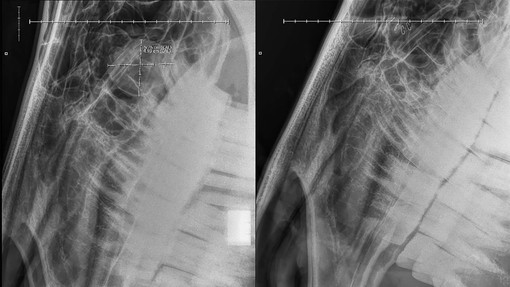

Discover more about the treatment of seven year old Christian, suffering from congenital flexural deformities of both distal interphalangeal joints (otherwise known as 'ballerina syndrome').